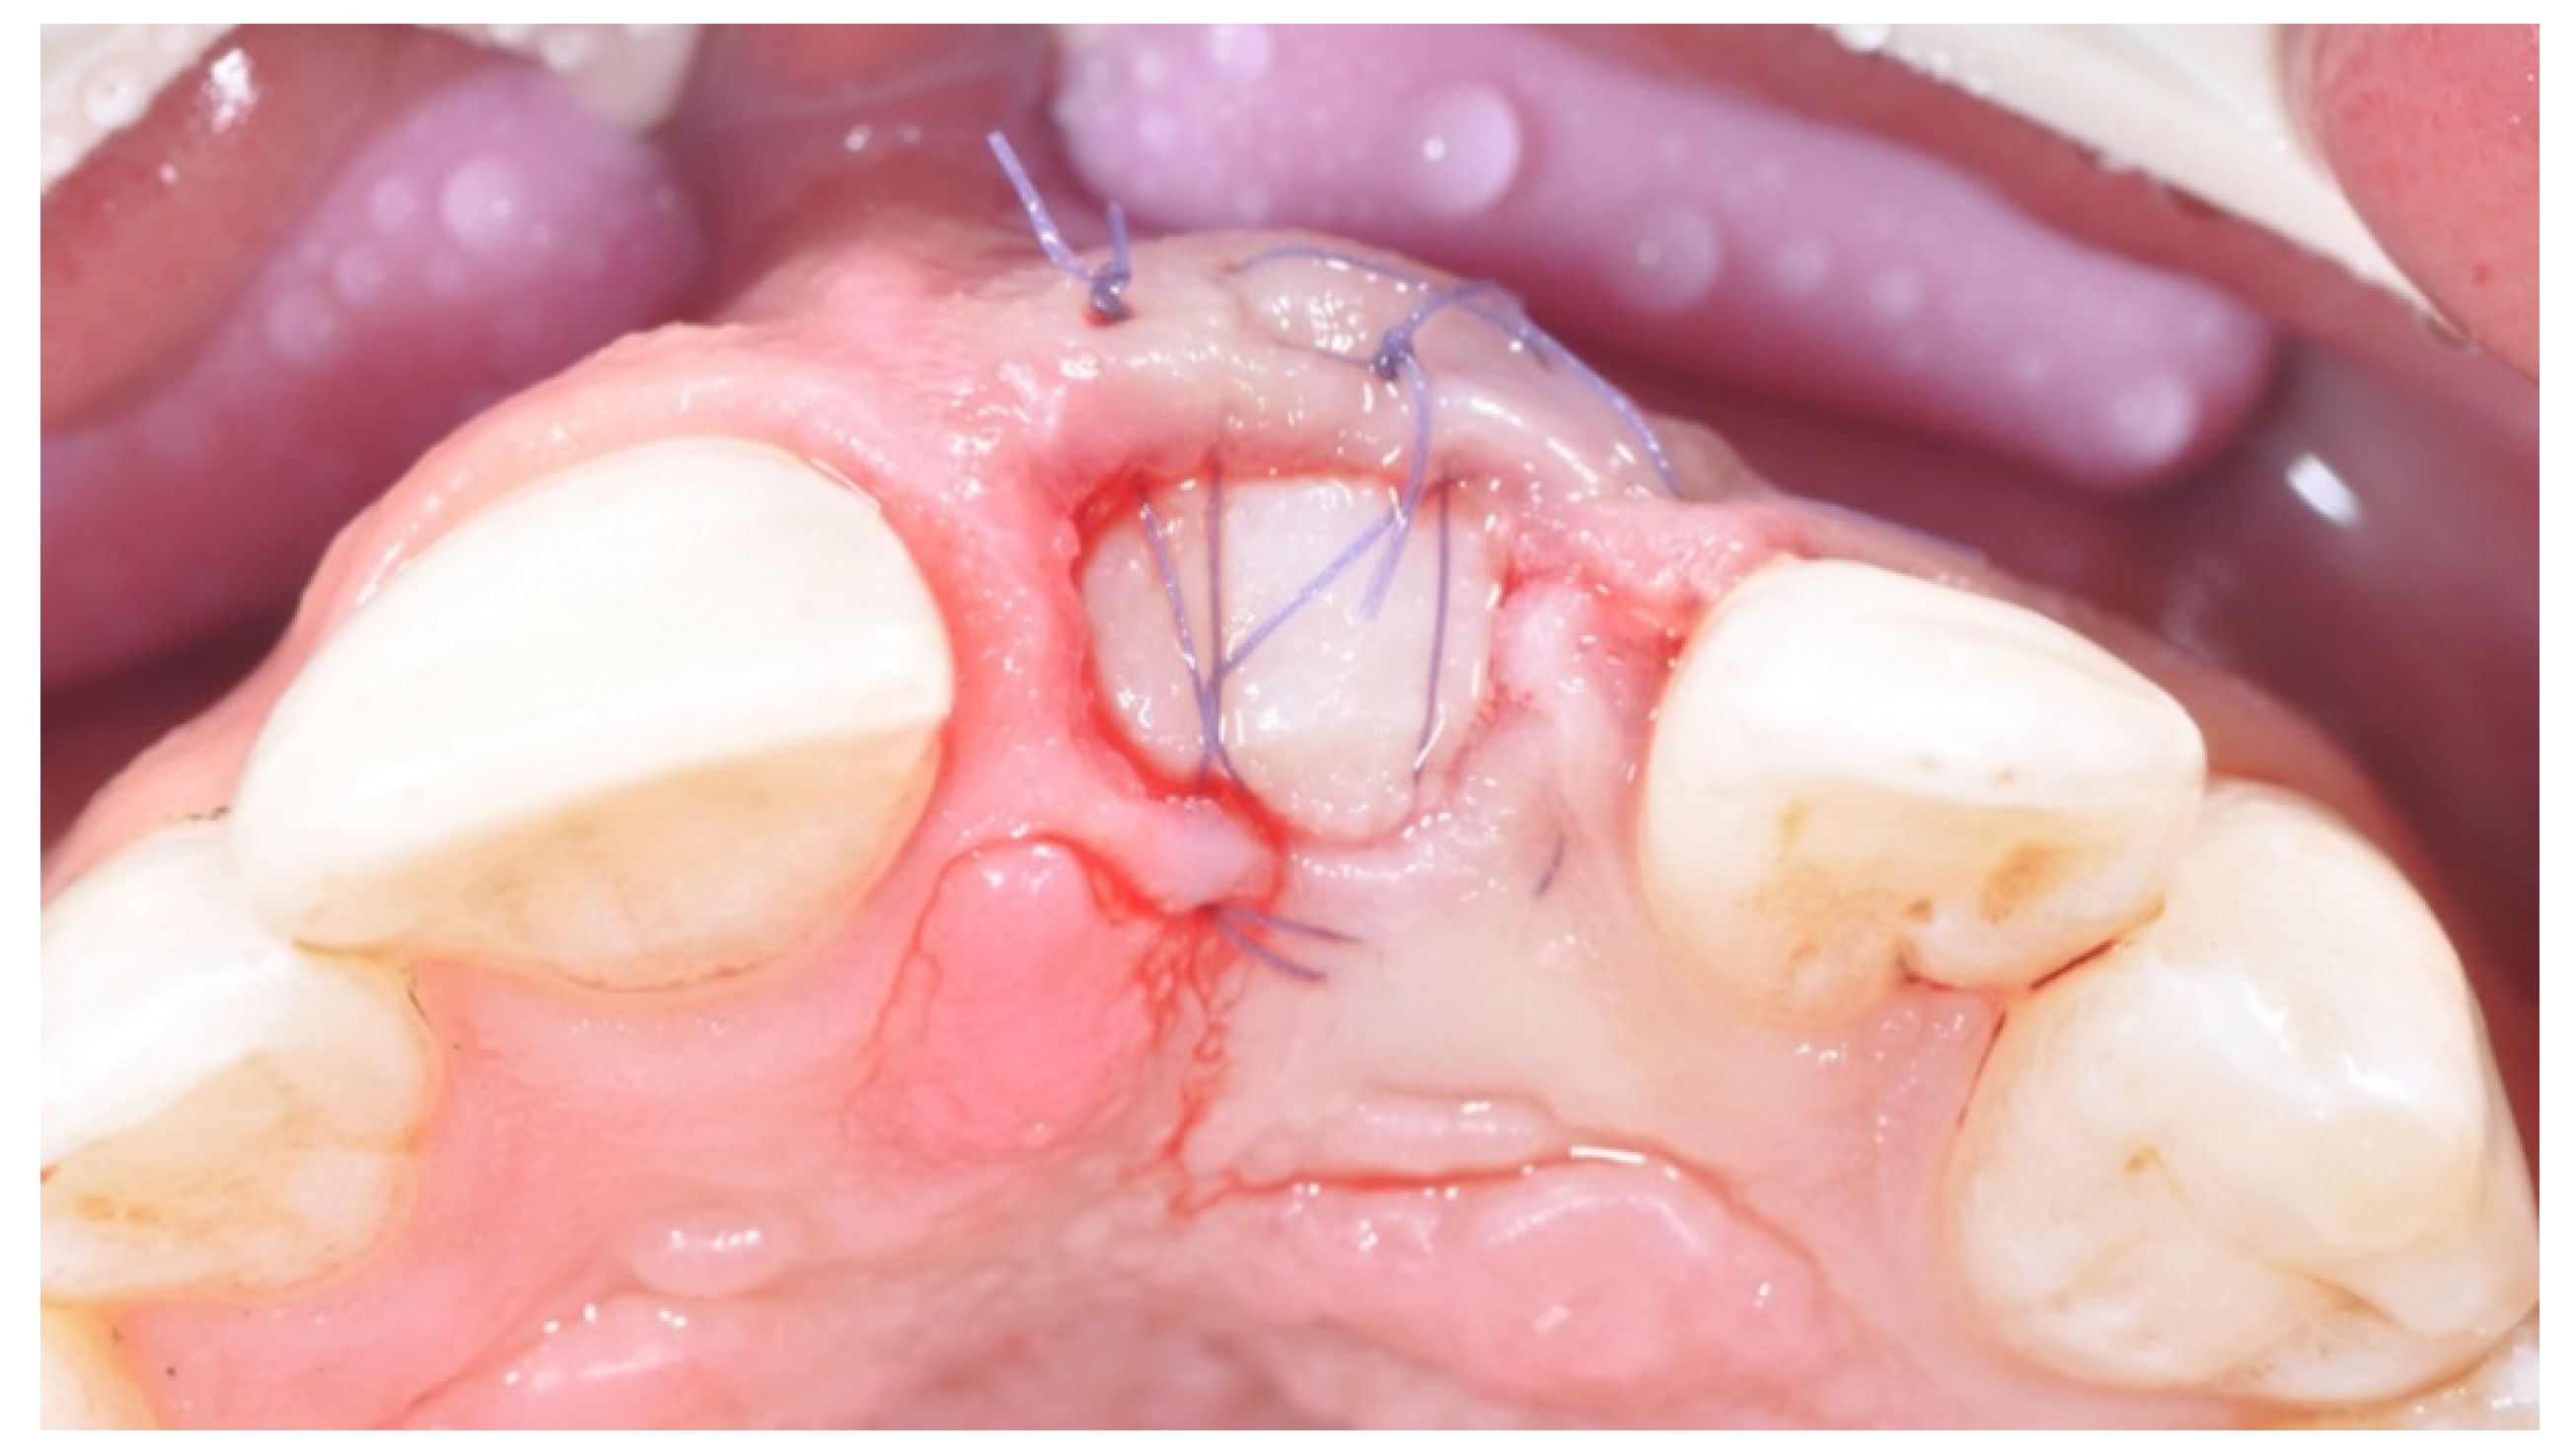

2. Case Presentation